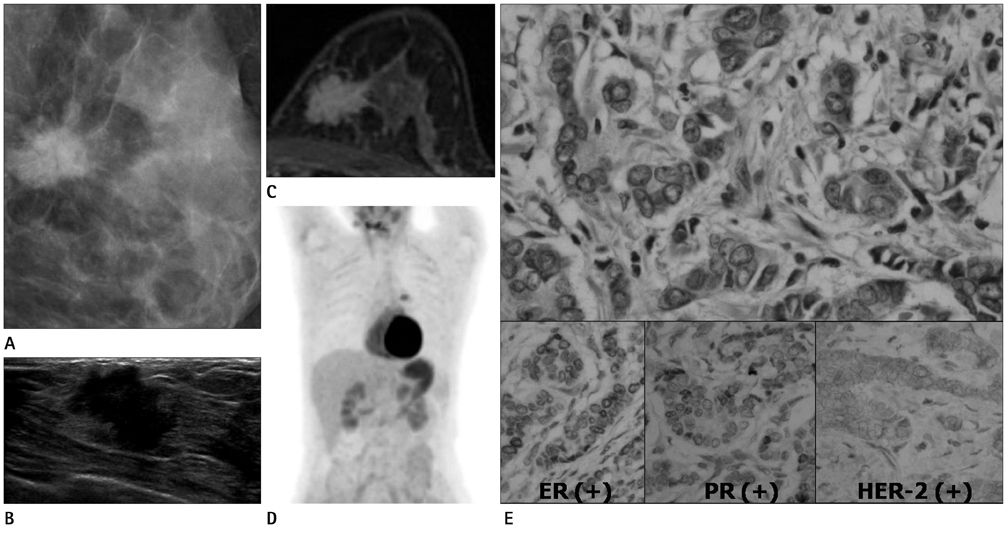

To retrospectively investigate the imaging [mammographic, ultrasonographic (US), magnetic resonance (MR) imaging] features and standardized uptake values (SUV) in positron emission tomography (PET)/computed tomography (CT) of triple-negative breast cancers (TNBC) and to compare them with breast cancers that are either estrogen receptor (ER) positive or progesteron receptor (PR) positive.

155 breast cancers cases were identified in 134 women (mean age, 51 years; range, 31-86 years). Surgically confirmed TNBC (n = 27) and ER-positive/PR-positive breast cancers (n = 81) were included among them. Cancers were investigated with mammography (n = 81), US (n = 106), MR imaging (n = 34) and PET-CT (n = 59). Mammographic findings are identified by detection of characteristic masses and microcalcifications. US findings included tumor size, margin, tumor shape, calcification and posterior shadowing. MR findings included tumor size, shape, margin, internal enhancement, intratumoral signal intensity and kinetics. Peak SUVs (p-SUV) of breast cancers were evaluated in PET/CT. These findings were compared with TNBC and ER/PR positive groups.

Mammographic findings had no significant association with the TNBC. High pathological grade (p < 0.05), larger than 2 cm in size, well-marginal mass, and round or oval-shaped (p < 0.05) is US were significantly associated with TNBC. In MR imaging, round mass shape (p < 0.05), well-circumscribed mass margin (p < 0.05), rim enhancement (p < 0.05), were significantly associated with TNBC. The peak SUV of TNBC tend to be higher than that of ER-positive/PR-positive breast cancer (7.95 +/- 5.50 vs. 4.91 +/- 3.00, p < 0.05).

TNBC tend to have high pathological grade, are of a large, round and smooth mass with rim enhancement on MR and US. In addition to above features, PET-CT with SUV estimation can improve the accuracy of test through the evaluation of TNBC.

Figure